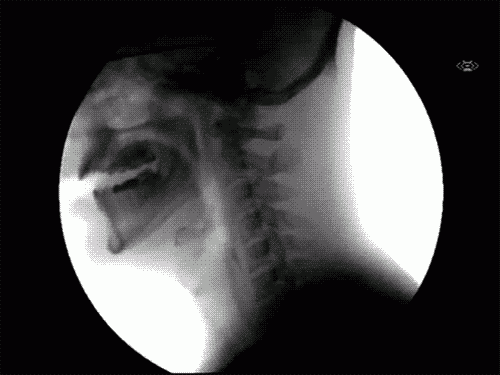

To se zgodi, ko pogoltnemo: